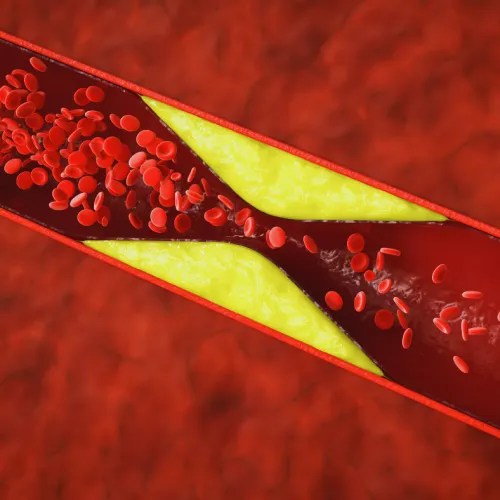

We offer minimally invasive, comfortable in-office treatments that effectively remove problem veins, relieve symptoms of venous reflux, improve circulation, and help your legs look younger. There are several options for vein treatment available. Varicose veins are swollen, twisted veins that show up just beneath the skin, usually on the legs and feet. They happen when tiny one-way valves in your veins don't work right, causing blood to collect and put pressure on the veins, making them bulge and twist.At Advanced Vascular & Vein, our interventional radiology team uses advanced imaging and minimally invasive methods to find and treat the real cause of varicose veins, not just the visible signs.

Varicose veins are caused by venous reflux, a failure of the

vein valves that normally keep blood flowing upward toward the heart. When

these valves weaken, blood flows backward and builds up in the veins, causing

visible swelling and discomfort.